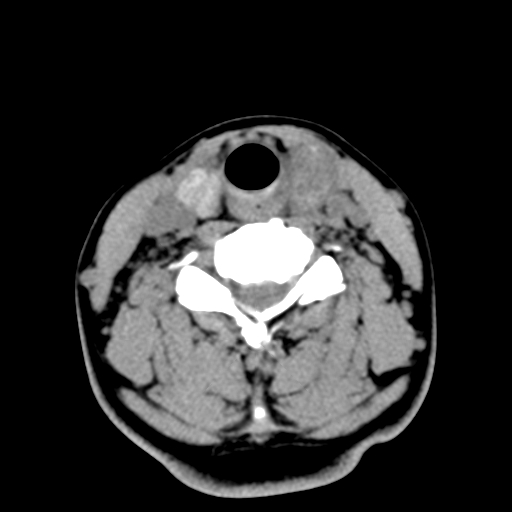

女,44岁,左颈部肿块伴疼痛两个月。患者不能做增强扫描。

左侧甲状腺明显肿大,密度不均匀性减低,正常之钙化基本消失,残留少许呈云雾状及颗粒状。其边缘不规则、不清晰,与前部联合处正常甲状腺不能分界不清,但尚可与周围其他组织分辨。颈动脉鞘区无明显淋巴结肿大。

多考虑:左侧甲状腺癌。

左侧甲状腺腺瘤或癌。甲状腺周围软组织间隙尚存在,喉软骨未见破坏征象,考虑腺瘤可能性大。

左侧甲状腺弥漫性肿大,密度减低,与气管及周围血管等分界清晰,颈部未见明显淋巴结肿大.首先考虑左侧甲状腺瘤;其次考虑甲状腺炎;不排除甲状腺癌可能.

多考虑甲壮腺腺瘤可能性大,周边的脂肪间隙显示尚清楚,未见明显肿大淋巴结.气管未见受压.